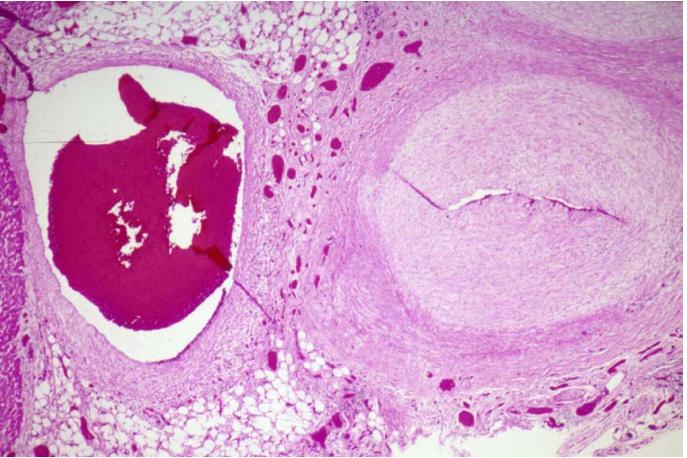

19月大儿童冠脉病理图。9月龄时罹患KD,10个月后死于冠心病。参考1

川崎病的主要并发症为冠状动脉异常(CAA),CAA可能导致心肌缺血、心肌梗死和猝死。通常最先通过超声心动图发现。CAA的分类依据是Z值(根据体表面积校正的冠状动脉内径)。

CAA位于心外膜冠状动脉,最常见于左前降支近端和右冠状动脉近端。按发生频率依次为:左冠状动脉主干、冠状动脉回旋支、右冠状动脉远端,以及冠状动脉后降支在右冠状动脉上的起始处。CAA好发于分支处,这提示了剪切应力的病理学作用。

CAA可以呈囊状、梭状或膨胀状(弥漫性扩张且无节段性动脉瘤)。其形状和大小随时间推移而演变。例如,最初表现为膨胀状的动脉瘤可在数周内演变为节段状或珠状。